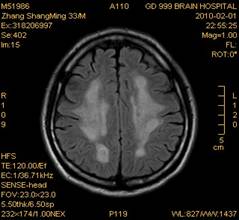

案例2 患者,女,30岁,二氯乙烷中毒性脑病的头颅MR。表现为双侧大脑半球皮层下白质、双侧外囊、双侧苍白球及双侧小脑齿状核内广泛片状、斑片状长T1长T2异常信号影,FLAIR序列呈高信号,增强后病变未见明显强化。

给予抗炎、脱水、疏通血管及营养神经等药物治疗。经过40天的对症治疗,痊愈出院。